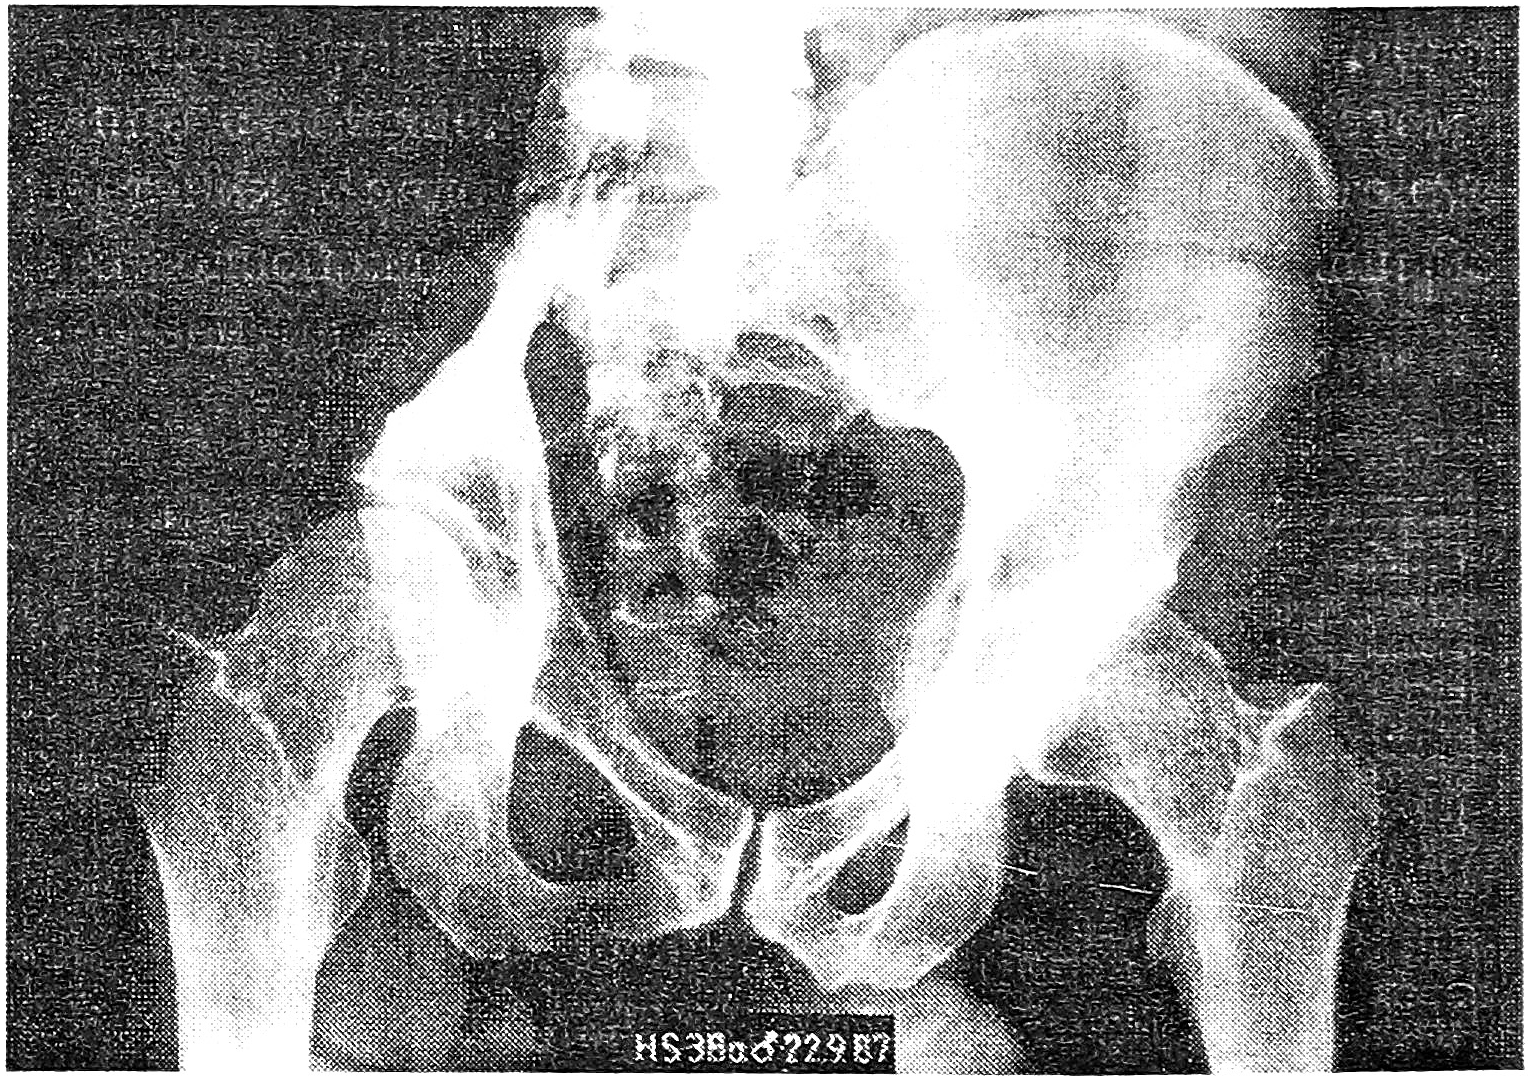

Рис. 3. Рентгенограмма больного 36 лет через 5 лет после резекции лонной кости и боковой массы таза справа по поводу остеосаркомы с замещением дефекта трансплантатом из большеберцовой кости.